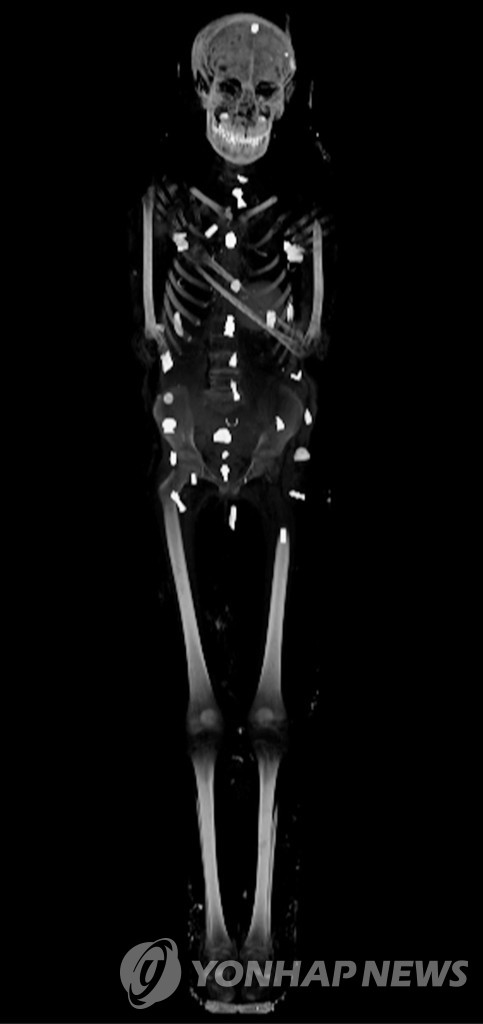

최근 미라에 접촉하지 않고도 내부를 살펴볼 수 있는 CT 스캔 방식이 도입되며 `황금 소년`의 모습이 마침내 세상에 알려지게 됐다.

CT 촬영 결과 이 황금 미라는 총 2개의 관으로 감싸인 형태로, 안쪽 나무관에는 금박을 입힌 얼굴 무늬가 새겨진 것으로 파악됐다.

소년의 나이는 사망 당시 14∼15세, 키는 128㎝ 정도로 추정됐다. 작은 코와 좁은 턱, 계란형 얼굴을 가진 아이였다.

특히 CT 사진에서는 소년의 입과 가슴 등에서 총 21가지 모양을 가진 다양한 부적 49개가 발견됐다. 대부분 금으로 만들어졌고, 준보석이나 구운 점토, 도자기 등이 쓰인 부적도 있었다.

망자의 심장 위치에 놓는 풍뎅이 모양의 황금 장식품 `하트 스카라베`를 비롯해 호루스의 눈, 타조 깃털, 두 손가락 등 부적도 몸 곳곳에서 찾아볼 수 있었다.

이 밖에도 소년의 발에는 관을 떠나는 데 도움을 주는 의미로 샌들이 놓여있고, 온몸은 이집트인들이 중요시했던 양치식물로 휘감겨 있다.